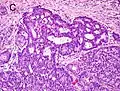

Gleason Pattern 3. H&E stain.

• Pattern 3 - The tissue still has recognizable glands, but the cells are darker. At high magnification, some of these cells have left the glands and are beginning to invade the surrounding tissue or having an infiltrative pattern. This corresponds to a moderately differentiated carcinoma.

Gleason 3

Gleason 3 is a clearly infiltrative neoplasm, with extension into adjacent healthy prostate tissue. The glands alternate in size and shape, and are often long/angular. They are usually small/micro-glandular in comparison to Gleason 1 or 2 grades. However, some may be medium to large in size. The small glands of Gleason 3, in comparison to the small and poorly defined glands of pattern 4, are distinct glandular units. Mentally you could draw a circle around each of the glandular units in Gleason 3.[4][7]